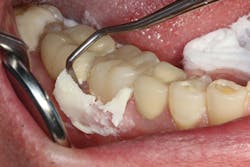

In the first case, a tooth with a subgingival margin preparation has been cleaned with an ultrasonic scaler and is gently dried in preparation for cementation. Note how the margin goes deeper subgingivally on the distolingual (figure 1). With TheraCem, a clean, prepped dentin or enamel surface is all that is needed to achieve excellent bond strengths, with the added benefit of sustained calcium and fluoride release. While TheraCem forms a strong bond to most substrates, including zirconia, a zirconia primer is still used prior to try-in to achieve optimal bond strength and prevent salivary contamination of the zirconia surface (figure 2).

Figure 1: Cleaned and prepared tooth